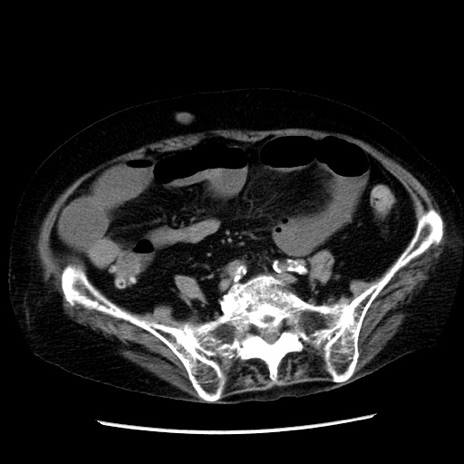

症例14(横断像)

【症例】 90歳代女性

【主訴】 腹痛・嘔吐

【現病歴】今朝から左側腹部痛を認めた。 経過観察していたが、嘔吐を認めたため来院。

【既往歴】 子宮癌術後

【身体所見】 意識清明、BP 127/54mmHg、P 98bpm Sp02 95%(RA)、BT 35.8°C、腹部平坦・軟腸ぜん動音聴取良好、右下腹部圧痛(+) 反跳痛なし

【データ】WBC 9800、CRP 0.46